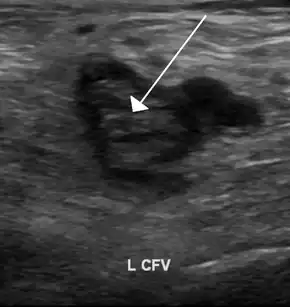

| An ultrasound image demonstrating a blood clot in the left common femoral vein. | |

The most common conditions associated with thrombophilia are deep vein thrombosis (DVT) and pulmonary embolism (PE), which are referred to collectively as venous thromboembolism (VTE). DVT usually occurs in the legs, and is characterized by pain, swelling and redness of the limb. It may lead to long-term swelling and heaviness due to damage to valves in the veins.[6] The clot may also break off and migrate (embolize) to arteries in the lungs. Depending on the size and the location of the clot, this may lead to sudden-onset shortness of breath, chest pain, palpitations and may be complicated by collapse, shock and cardiac arrest.[2][7]